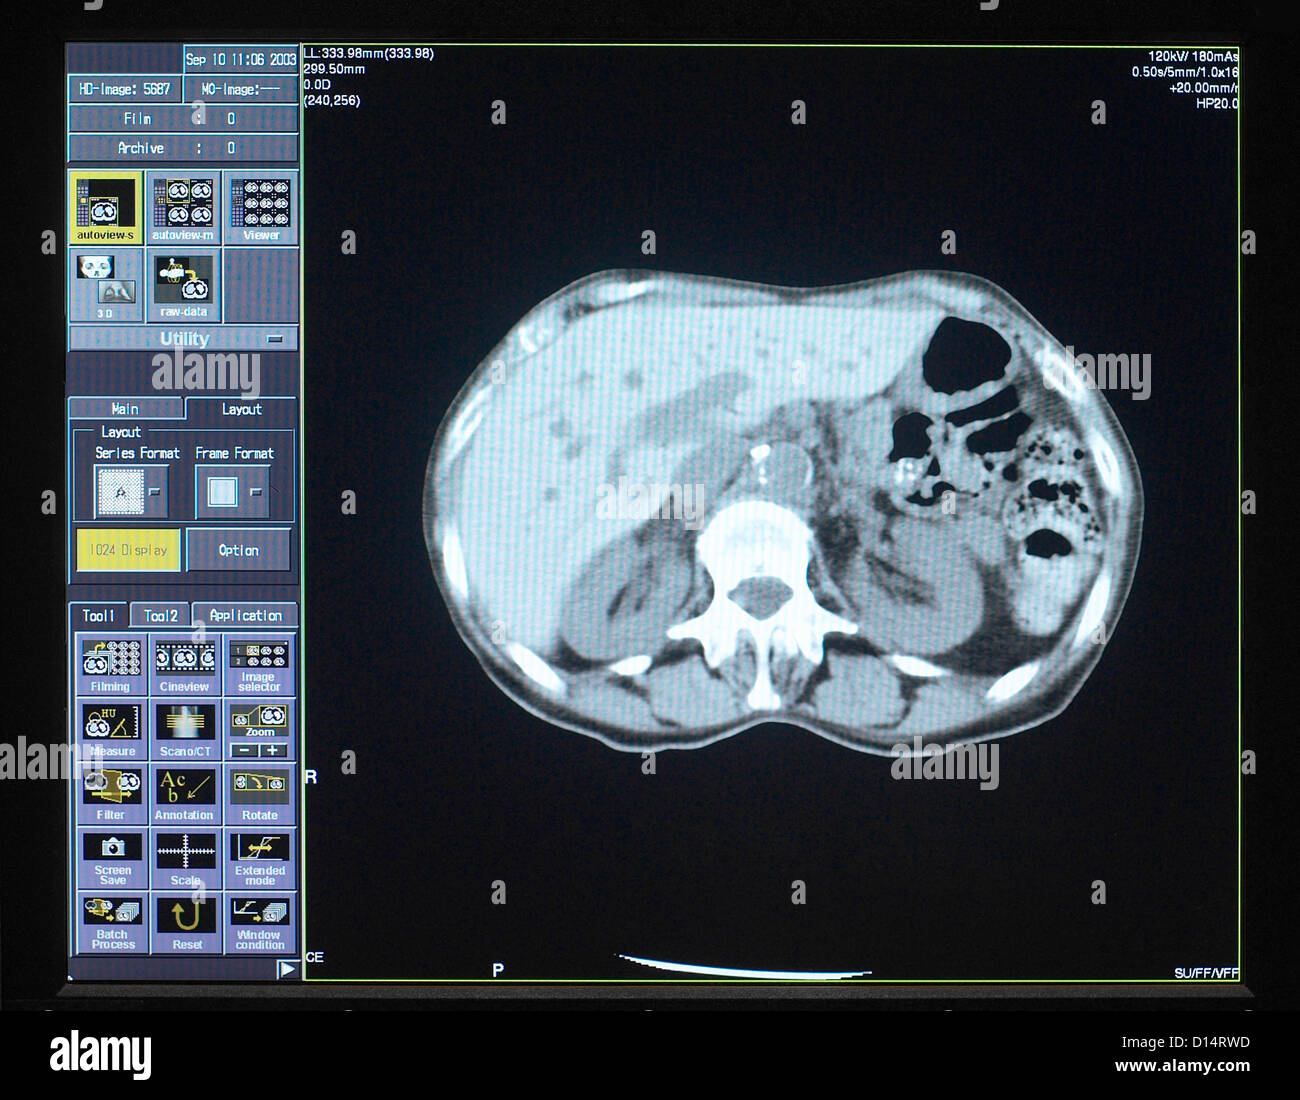

Brain Scan Image Banque D'Imageshttps://www.alamyimages.fr/image-license-details/?v=1https://www.alamyimages.fr/photo-image-brain-scan-image-52352313.html

Brain Scan Image Banque D'Imageshttps://www.alamyimages.fr/image-license-details/?v=1https://www.alamyimages.fr/photo-image-brain-scan-image-52352313.htmlRMD14RWD–Brain Scan Image